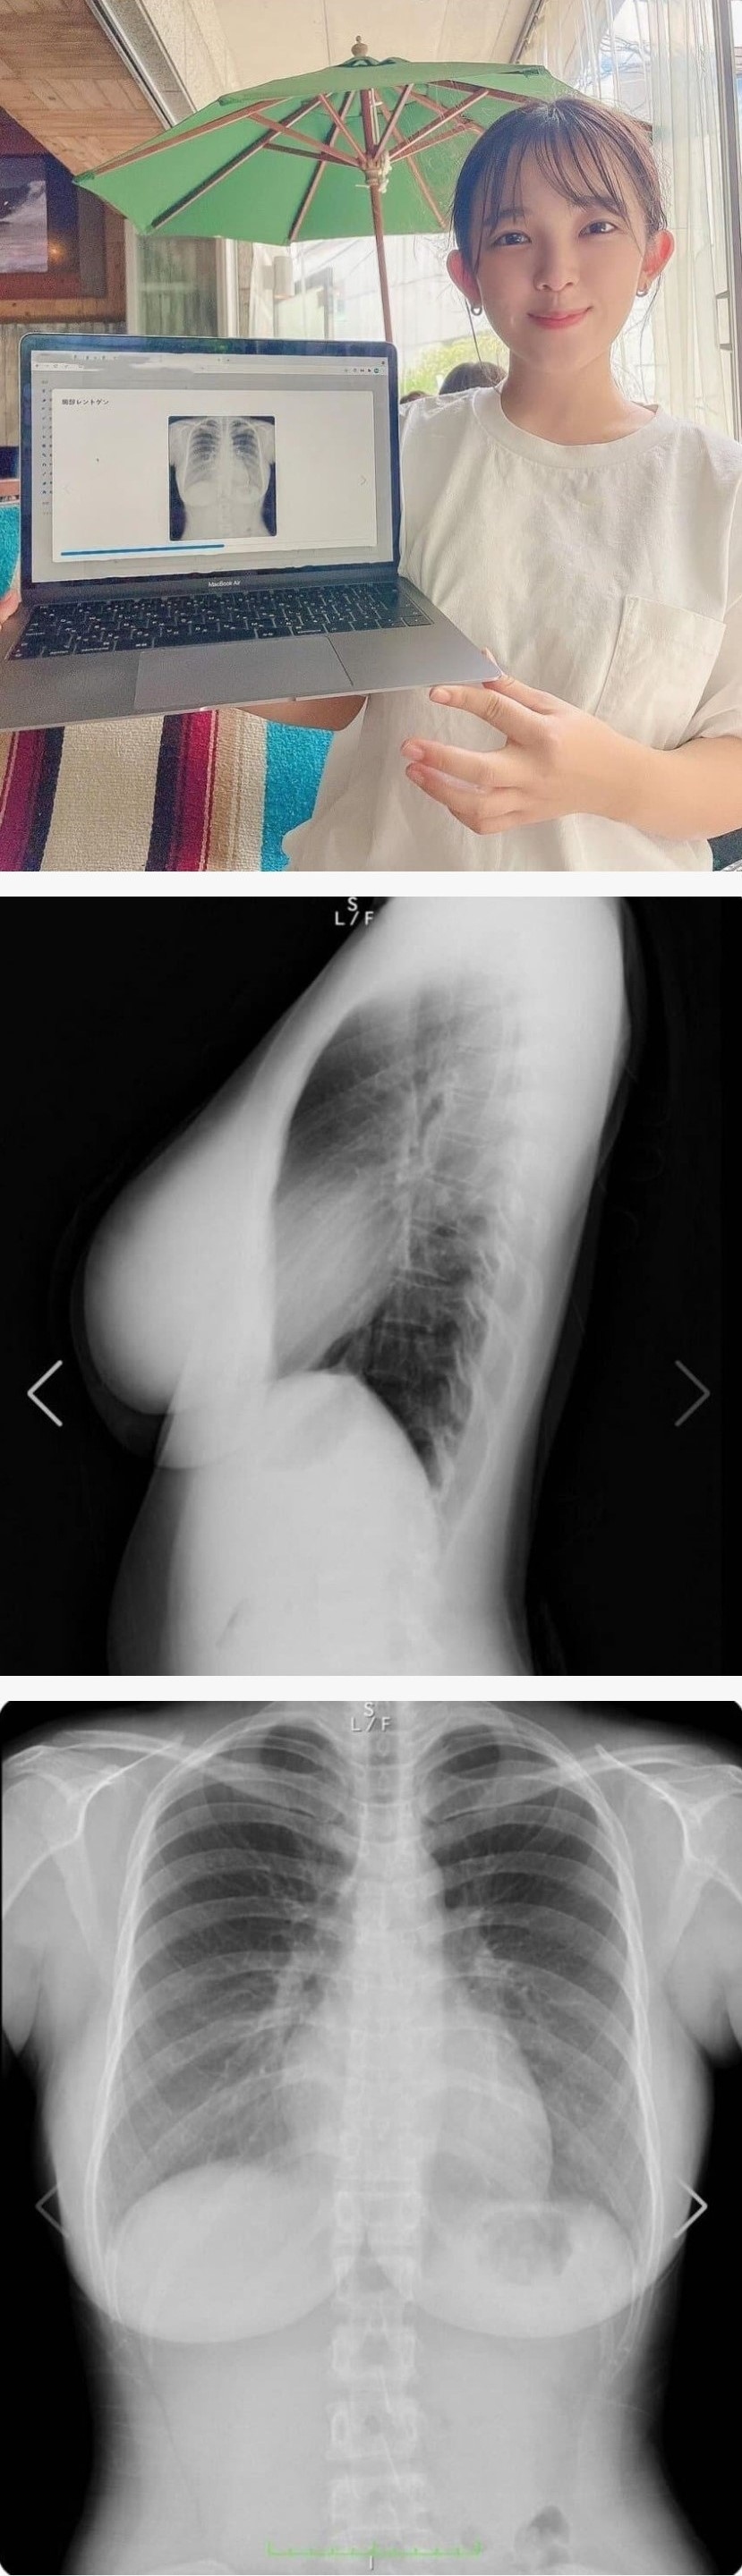

자연산 가슴 인증한 그라비아 아이돌 아마키 쥰

척추도 이쁘네요~